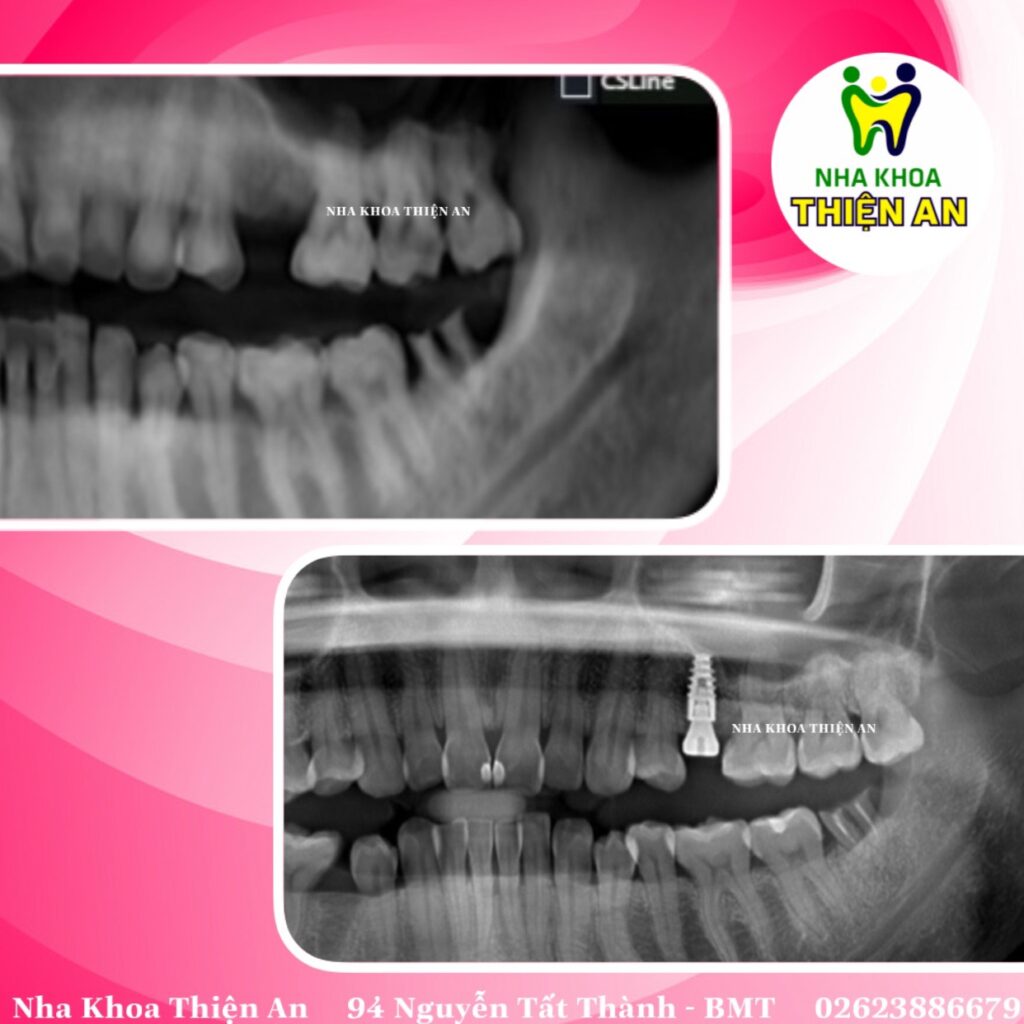

Trồng implant thay thế răng mất cho c bệnh nhân dễ thương với máng hướng dẫn phẫu thuật tại nha khoa Thiện An BMT – Đăk Lăk

Ưu điểm của máng hướng dẫn phẫu thuật cấy ghép Implant là cho phép lập kế hoạch cấy ghép hoàn chỉnh trước cả khi phẫu thuật diễn ra. Giúp quá trình phẫu thuật diễn ra chính xác tuyệt đối, tỷ lệ thành công cũng như mức độ an toàn luôn được đảm bảo

Implant replacement teeth for cute patients with surgical guide trays at Thien An BMT dental clinic – Dak Lak

The advantage of the implant surgery guide is that it allows for complete implant planning before surgery takes place. Helping the surgical process to take place with absolute precision, the success rate as well as the safety level are always guaranteed